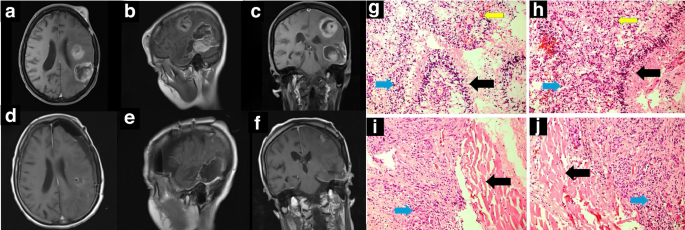

After eighteen months, she developed new neurological symptoms, including right-sided weakness, memory problems, and difficulty speaking. MRI revealed multifocal recurrence in the left frontal and temporal lobes, including near the surgical site. Due to the involvement of critical brain areas, she underwent awake craniotomy and complete resection of all lesions, including an extra-neural GB metastasis in the scalp. The pathological analysis confirmed wild-type IDH-1&2, mutated TERT, non-mutated BRAF, EGFR, and non-methylated MGMT (Supplementary S3-S7). The pathological diagnosis was a malignant tumor (Fig. 1), and immunohistochemical (IHC) examination (Fig. 2) confirmed that the diagnosis was consistent with the recurrence and metastasis of GB; the examination also demonstrated the following: β-catenin (negative), Desmin (negative), glial fibrillary acidic protein (GFAP) (positive), Myogein (negative), p53 (negative), SMA (Alpha Smooth Muscle Actin) (negative), and Vimentin (positive). In our IHC analysis, GB samples exhibited positive staining for GFAP and vimentin, which are associated with the mesenchymal transition. These markers’ expression indicates cellular plasticity and has been linked to increased invasive potential and metastatic behavior in glioblastoma. The positivity for GFAP and vimentin in our samples supports the hypothesis that these cells are undergoing a metastatic transition, consistent with the aggressive nature of GB progression [21,22,23,24].

Axial (a), sagittal (b), and coronal (c) views of brain MRI before the second surgery, along with the postoperative counterparts (d–f). In the preoperative imaging, multicentric GB involving left posterior frontal and left temporoparietal regions concomitant with metastasis to the scalp of the left frontal area is seen. Compared to postoperative imaging, gross total removal (GTR) of the lesions has been obtained. g Hypercellular neoplastic glial tissue (blue arrow) with palisading necrosis (black arrow) and vascular proliferation (yellow arrow) (hematoxylin-eosin, x200). h Hypercellular neoplastic glial tissue (blue arrow) with vascular proliferation (yellow arrow) and palisading necrosis (black arrow) (hematoxylin-eosin, x200). i Neoplastic glial tissue (blue arrow) with invasion to muscle bundles (black arrow) (hematoxylin-eosin, x200). j Neoplastic glial tissue (blue arrow) invades muscle bundles (black arrow) (hematoxylin-eosin, x200).